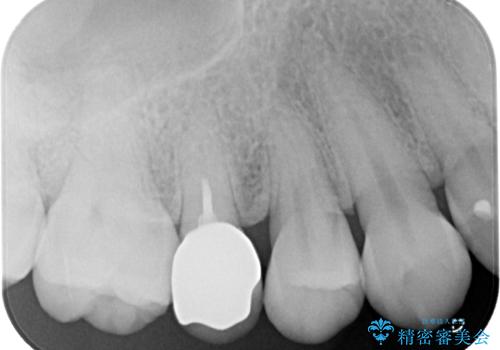

銀歯の歯は既に根管治療がされており、根尖部に病変が認められないため、根管治療を行うことなくオールセラミッククラウンにて補綴治療を行うこととしました。

やはりむし歯は大きく、一部歯髄を切除することとなりましたが、その後は良好な経過をたどっています。